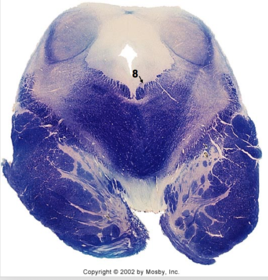

| Nucleus gracilis | |

| Accessory nucleus | |

| Medial longitudinal faciculus | |

| Pyramidal decussation | |

| Medullary pyramids | |

| Anterior spinocerebellar tract | |

| ALS | |

| Posterior spinocerebellar tract | |

| Spinal tract of V | |

| Spinal nucleus of V | |

| Nucleus cuneatus | |

| Fasciculus cuneatus | |

| Fasciculus gracilis | |

| Central canal | |

| Internal acruate fibers | |

| Lateral (external/accessory) cuneate nucleus | |